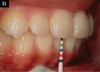

Recording the lower dental midline in relation to the midline of teeth Nos. 8 and 9 at the patient's initial visit and at subsequent recare appointments is considered a "rapid screen" for change in the TMJ complex (Figure 1).

Fig 1. Recording the lower dental midline in relation to the midline of teeth Nos. 8 and 9 at the patient’s initial visit and at subsequent recare appointments is considered a “rapid screen” for change in the TMJ complex.

Figure 1